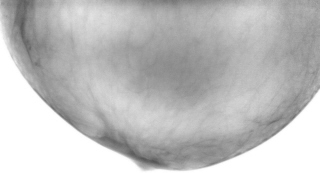

Иллюстрации 4, 5 – фрагменты с увеличением. Довольно четко дифференцируется «внутренний контур». От указанного участка четко визуализируются линейные структуры, направленные в сторону верхнего наружного квадранта.

Иллюстрация 6. В зоне измененной структуры кальцинаты.

Вывод. По всей видимости, с большей степенью вероятности, можно предположить локальное развитие соединительной ткани, возможно в результате перенесенного воспалительного процесса или травмы. В проведении дифференциальной диагностики необходимо иметь ввиду (с учетом локализации) рак Педжета.